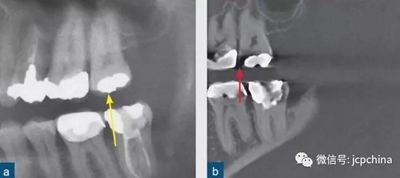

(a)根尖片。

(b)CBCT矢狀面。

同一解剖位置顯示出的廣泛射線硬化偽影,使CBCT分辨金屬邊緣變得困難。CBCT圖像中27牙的近中壁缺損可能為齲損(紅色箭頭),而根尖片(黃色箭頭)卻顯示正常。